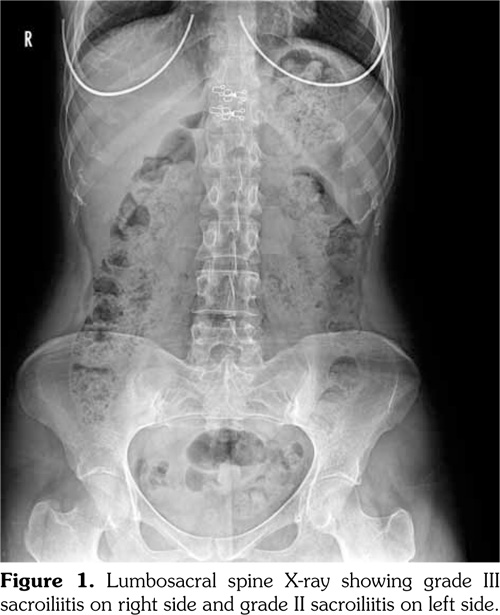

Schirmer’s test (right 3 mm, left 5 mm) and tear break-up time values (right 5 seconds, left 6 seconds) were consistent with dry eye. Lumbosacral spine X-ray showed grade III sacroiliitis on the right side and grade II sacroiliitis on the left side (Figure 1). Sacroiliac magnetic resonance imaging revealed acute inflammatory changes and bilateral sacroiliitis with moderate chronic features (Figure 2).